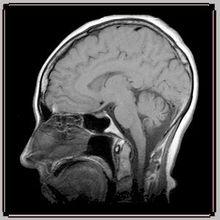

血氧水平依賴(blood oxygen level dependent, BOLD)效應最先是由 Ogawa 等於1990 年提出, 他們發現氧合血紅蛋白含量減少時, 磁共振信號降低, 並且還發現信號的降低不僅發生在血液里, 而且還發生在血管外, 於是認為這種效應是血液的磁場性質變化引起的。此後很多研究者進行了大量的理論和實驗的工作, 總結出 BOLD-fMRI 的成像基礎,神經元活動時, 局部腦血流量和耗氧量均增加, 但是兩者增加有差異, 即腦血流量的增加多於耗氧量的增加, 這種差異使活動區的靜脈血氧濃度較周圍組織明顯升高,去氧血紅蛋白相對減少。去氧血紅蛋白是順磁性的物質, 在血管和其周邊產生局部梯度磁場,使質子快速去相位, 因而具有縮短 T2 的作用。 腦區激活時, 由於去氧血紅蛋白減少, 縮短 T2 的作用也減少, 同靜息狀態相比, 局部腦區的 T2 或 T2F 相對延長, 因而在 T2 加權或者 T2F 加權的功能磁共振成像圖上表現為信號相對增強。